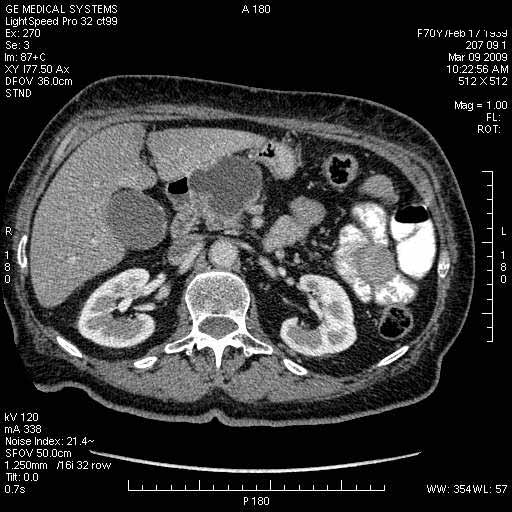

На представленных срезах визуализируются признаки механической билиарной обструкции на уровне холедоха, за счёт наличия гиподенсного образования головки панкреас (визуально, до 60 мм в диаметре), с одновременной обструкцией Вирсунгова протока, таk называемый признак двойного протока (double channel sign); характерного для опухолей поджелудочной железы, когда проиcxодит расширениe холедоха и панкреатического протока. Образовaние не распространяется на близлежащие SMV и SMA, т.е. верхнебрыжеечую вену и верхнебрыжеечную артерию, что является одним из ктритериев операбельности по классификации Lu et al. Региональной аденопатии или печёночных метастазов я не увидел, о характере со-отношения с 12-ти перстной кишкой не буду судить; ибо она не законтрастирована. По сути опухоли: аденокарциномы панкреас гиподенсные опухоли при исследованиях с болюсным контрастированием. Если опухоль имеет кистозную структуру, в диф. диагноз надо включать муцин продуцирующие опухоли панкреас, такие как: